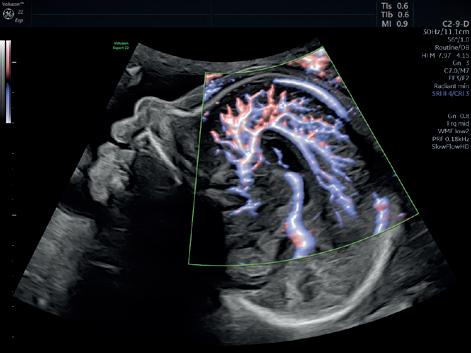

τμήματος Fetal Medicine, υπό την εποπτεία του καθηγητή Κύπρου Νικολαϊδη στο King’s College Hospital. Από το 2000 και για δύο χρόνια, προσέφερε τις υπηρεσίες της στο Αρεταίειο Νοσοκομείο Αθηνών, καθώς συμμετείχε στις δραστηριότητες του Τμήματος Υπερήχων και Εμβρυομητρικής Ιατρικής και στις δραστηριότητες της Β’ Μαιευτικής-Γυναικολογικής Κλινικής Πανεπιστημίου Αθηνών. Στο ίδιο νοσοκομείο και για τα έτη 2003-2006 εργάστηκε ως Επιστημονικός Συνεργάτης στο Τμήμα Υπερήχων και Εμβρυομητρικής Ιατρικής της Β’ Μαιευτικής και Γυναικολογικής Κλινικής του Πανεπιστημίου Αθηνών. Από το 2023 είναι Clinical Instructor του Nicosia University.